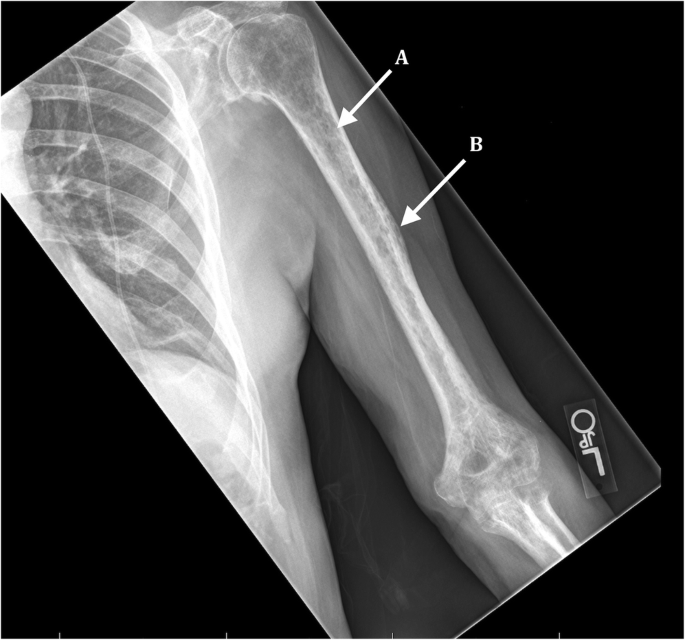

Get Multiple Myeloma Bone Lesions Prognosis US. It defines the factors that influence patient survival. Lytic lesions (areas of bone damage).

It defines the factors that influence patient survival. Bone disease in multiple myeloma includes lytic lesions, plasmacytomas and vertebral compression fractures. Multiple myeloma, the most common bone malignancy, is occurring with increasing frequency in older persons. The median survival in the prechemotherapy era was about 7 months.